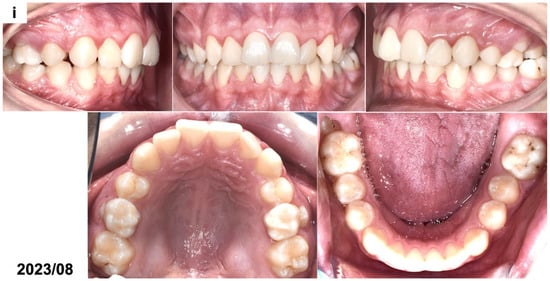

(a) Intraoral photographs before surgical and orthodontic treatment. The patient was 8 years and 10 months old. (b) Panoramic radiograph before the treatment, presenting the odontogenic tumor in the left mandible molar region (OCx = complex odontoma). The patient was 8 years and 10 months old. (c,d) Intraoral photographs taken during the surgical removal of the tumor exposing the occlusal surface of the permanent lower left first molar (OCx = complex odontoma, LM1 = lower left first permanent molar). The patient was 8 years and 11 months old. (e) Panoramic radiograph after the surgical treatment and bonding of the orthodontic attachment (OA = orthodontic attachment). The patient was 8 years and 11 months old. (f) Panoramic radiograph 1 year after the removal of the tumor showing the orthodontic attachment bonded to the occlusal surface of the permanent lower left first molar (OA = orthodontic attachment). The patient was 10 years and 1 month old. (g) Intraoral photographs of spontaneously erupted permanent lower left first molar after removal of the orthodontic attachment. The patient was 10 years and 11 months old. (h) Panoramic radiograph 4 years after the surgical and orthodontic treatment (LM1 = lower left first permanent molar). The patient was 12 years and 7 months old. (i) Intraoral photographs 4 years after the surgical and orthodontic treatment showing the erupted permanent lower left first molar and its position in the dental arch. The patient was 12 years and 7 months old.

The lower removable plate with an extension to attach the elastic from the button bonded on the exposed impacted molar was prepared in March 2020. However, due to the eruption of the COVID-19 pandemic, it was not delivered to the patient after surgery. The university clinic was only treating emergencies for the next few months, and the patient came back after 1 year, in February 2021. The patient reported a spontaneous eruption of the impacted maxillary. The occlusal surface of the lower left first permanent molar with a bonded button was visible during the clinical examination. The panoramic radiograph (Figure 1f) revealed a distinct occlusal movement of the impacted tooth and normal healing after the removal of the tumor. In December 2021, the mandibular left first permanent molar erupted in the oral cavity (Figure 1g). No pathologies were present on the panoramic radiograph except for the bending of the distal root of the affected molar. The patient has received an activator with an expansion screw to correct his Class II relations and maxillary crowding. In August 2023, the impacted molar tooth erupted into occlusion, and the root development was finished (Figure 1h,i). A marked dilaceration of its distal root could be noticed, which was caused by the presence of a tumor in proximity to the developing, neighboring first molar. The prognosis of the affected molar was estimated as favorable in the long term if good oral hygiene is maintained. A complete regeneration of the alveolar bone defect was also seen. No other permanent molars on the side of the tumor were present on the radiograph. Orthodontic treatment with a removable appliance is continued.